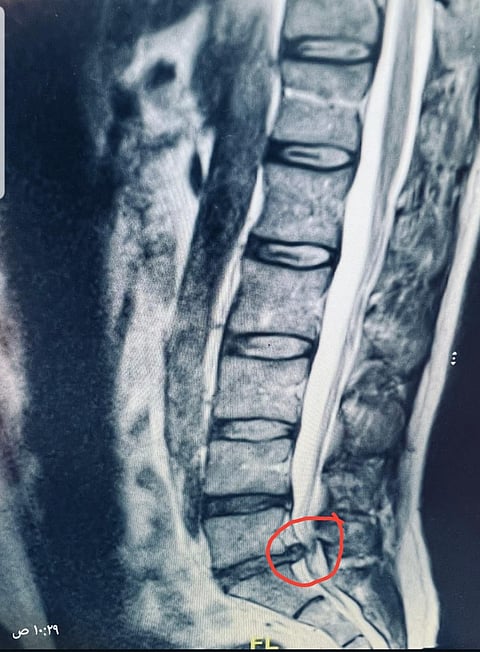

وأضاف: تم فحص المريض وبمناظرة أشعة الرنين المغناطيسي تبين وجود انزلاق غضروفي كبير تسبب في الضغط على العصب الطرفي بين الفقرة القطنية الخامسة والعجزية الأولى.

وأشار "الحميدان" إلى أنه على الفور أجريت العملية باستخدام الميكروسكوب وإزالة الغضروف المتسبب في الضغط على العصب بصورة كاملة وتوسيع مسار العصب الطرفي.